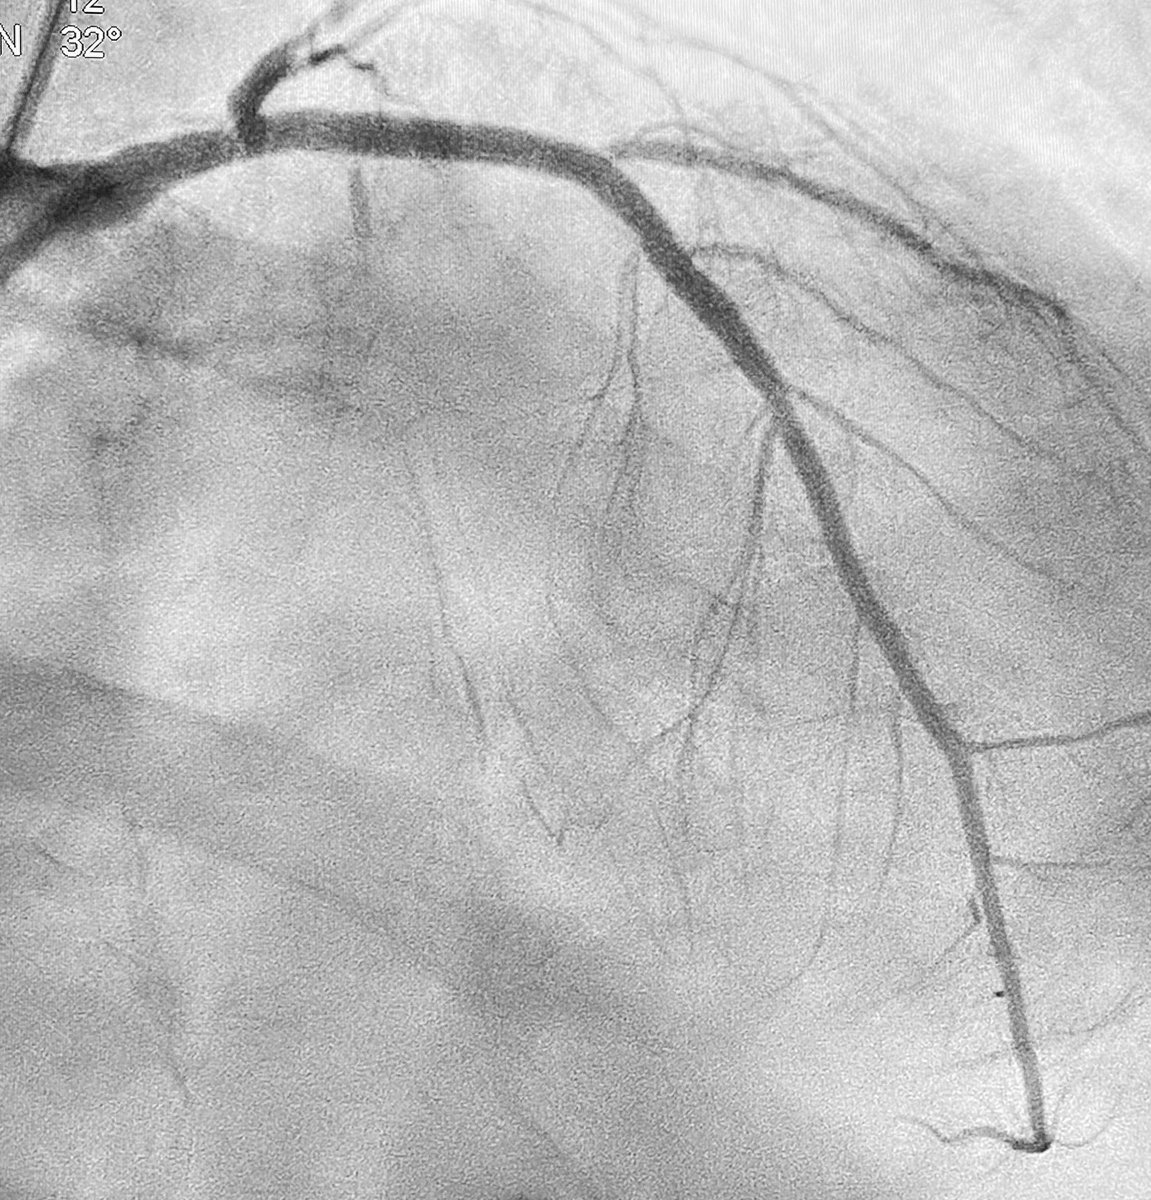

.@DrNjambi of @MGHHeartHealth received @SCAI-WIN's Complex and High-Risk Interventional Procedures (CHIP) award. The award enables #cardiology fellows or practicing cardiologists to pursue an additional year of advanced training on work in the cardiac catheterization lab. (1/2)